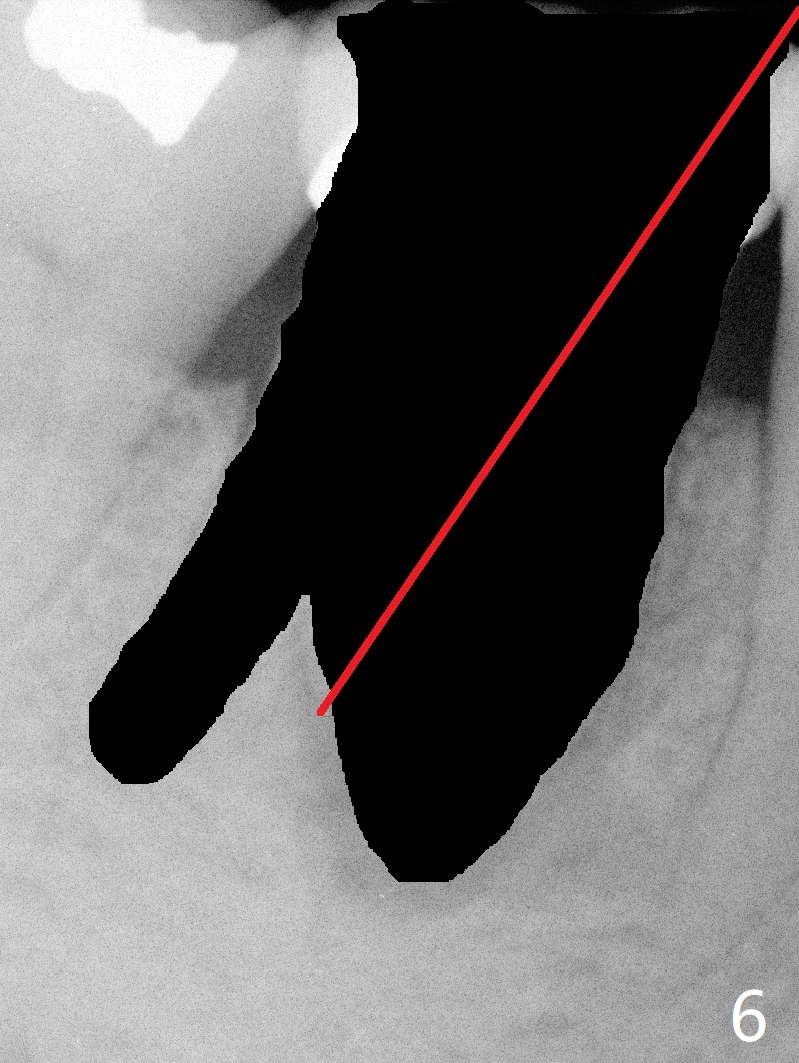

A 55-year-old woman has severe bone loss (Fig.1 with buccal and lingual fistulae) around the mesial (M in Fig.2) and distolingual (DL) roots. If there is a septum after extraction (Fig.3 S), osteotomy will be established in the septum to enhance primary stability (Fig.4). When the septum cannot be saved (Fig.5), osteotomy is to be initiated in the septal slope oblique (Fig.6 <). The osteotomy will be straightened once an entry is made (Fig.7). The initial osteotomy is slightly distal, since as osteotomy increases (Fig.8 blue), it tends to shift mesial (arrow). In addition, the apex of the 2nd bicuspid tilts distal (yellow dashed line). Depth of osteotomy is 20 mm (crest, Fig.9) or 18 mm (septum) so that 8 mm of the native bone can be obtained with 3 mm clearance from the Inferior Alveolar Canal (red dashed line). PRFx2 is required (seems not done).